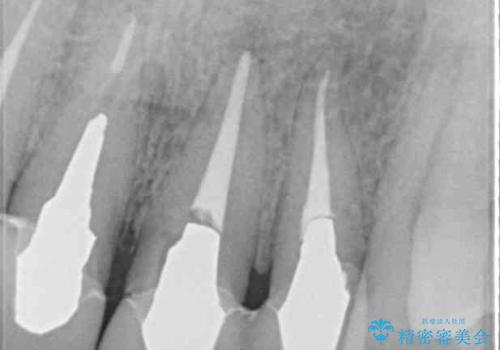

- 昨年治療した前歯の根尖部に痛みを感じ、ラバーダムや顕微鏡を用いた根管治療を希望されて、転院された患者様です。

前医にて神経を取り除いた処置を行った際、ラバーダムが使用されなかったとのことで転院されてきました。

根管治療を実施した後、オールセラミッククラウンに補綴することとしました。